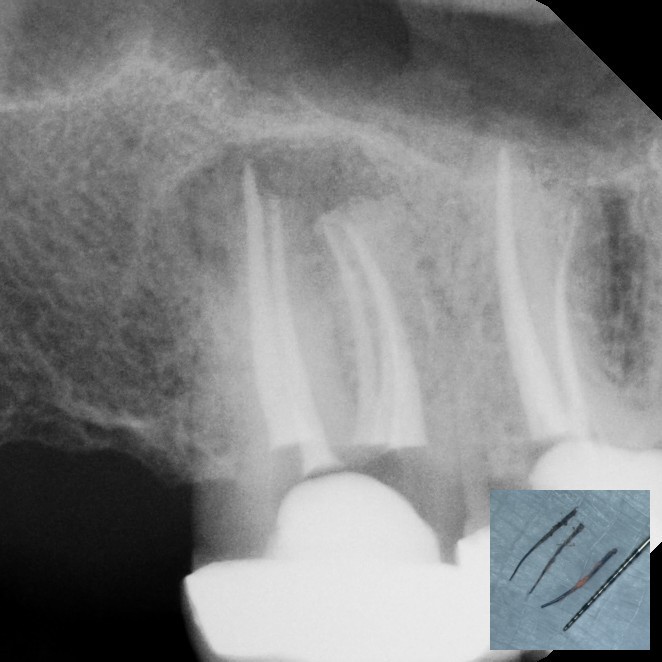

Periapical Surgery

Endodontic surgery is a specialized dental procedure used to treat problems at the tip of a tooth's root or in the surrounding bone when standard root canal therapy isn't enough. The most common type, called an apicoectomy, involves making a small opening in the gum to access the root tip, removing infected tissue, and sealing the end of the root to prevent the infection from returning. This allows us to save the natural tooth and restore oral health, even in cases where other treatments have failed.

While it may sound complex, modern endodontic surgery is precise, minimally invasive, and performed under local anesthesia for your comfort. Most patients are surprised at how quick and straightforward the procedure is, and recovery is typically fast. Choosing endodontic surgery can help you avoid extraction, preserve your natural bite, and prevent the need for more extensive dental work in the future.